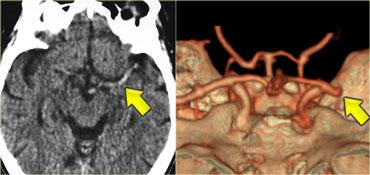

Dấu hiệu MCA tăng tỷ trọng (Dense MCA sign)

Dấu hiệu này là kết quả của huyết khối hoặc thuyên tắc trong MCA.

Hình bên trái là bệnh nhân có dấu hiệu MCA tăng tỷ trọng.

Trên CT mạch máu (CTA), tắc MCA được hiển thị rõ ràng.